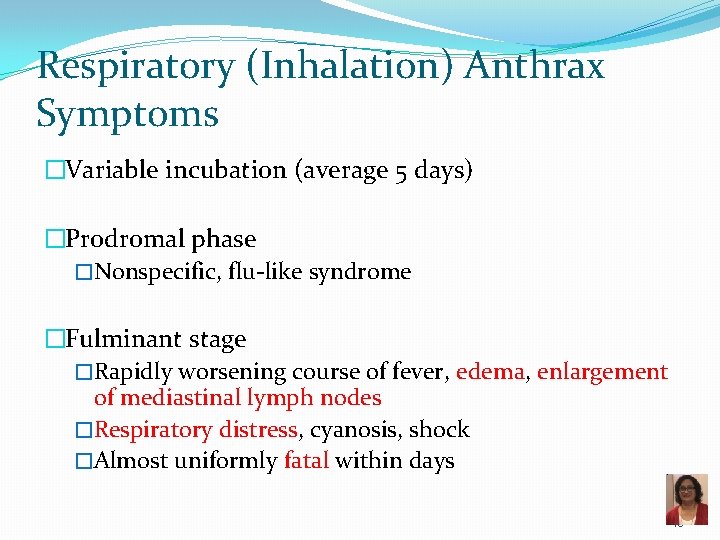

Respiratory (Inhalation) Anthrax Symptoms �Variable incubation (average 5 days) �Prodromal phase �Nonspecific, flu-like syndrome �Fulminant stage �Rapidly worsening course of fever, edema, enlargement of mediastinal lymph nodes �Respiratory distress, cyanosis, shock �Almost uniformly fatal within days 45